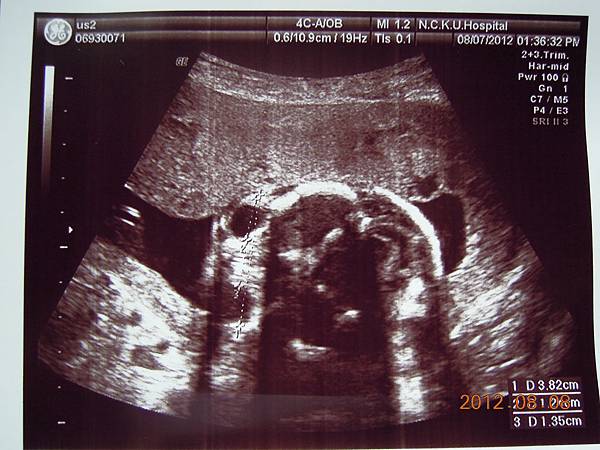

這個好像是逼逼的臉吧~~

這張可以看到他的厚嘴巴~~我回來拿給Horry看,說他跟你的嘴巴一樣ㄟ~~他聽了一直笑~~~